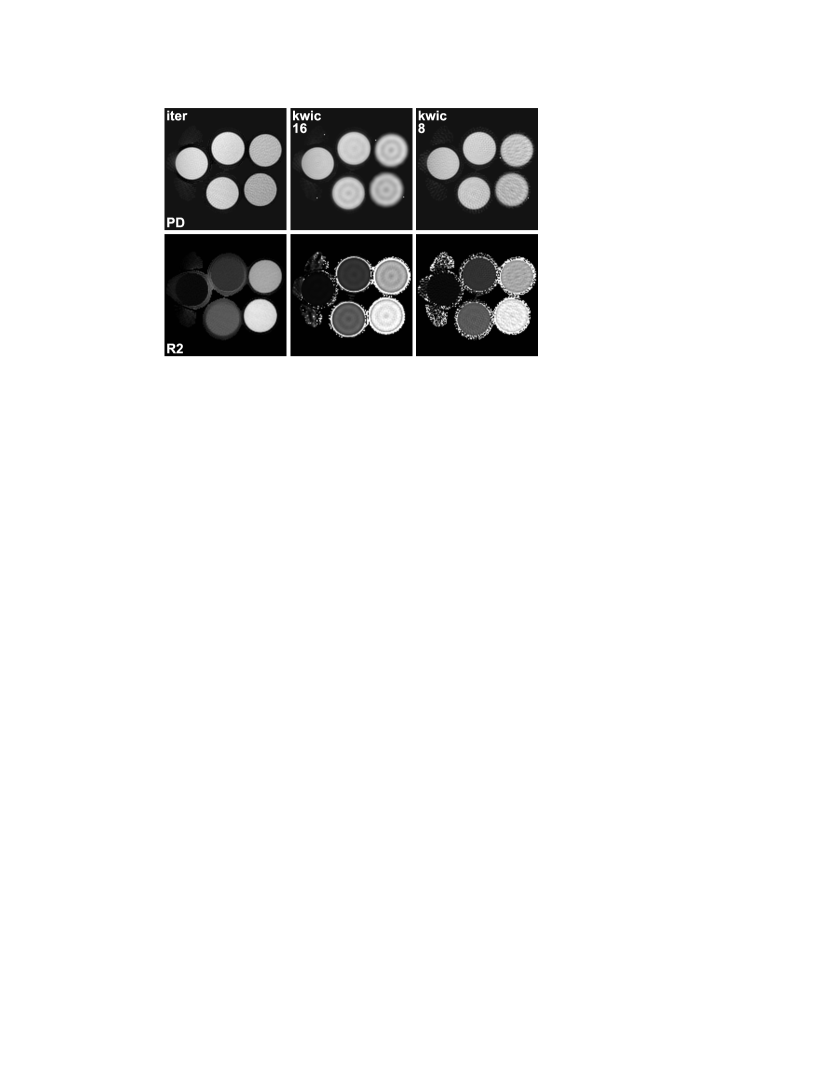

Figure 1 compares spin-density and relaxivity maps for a phantom containing five water-filled tubes with different concentrations of , i.e. different T2 relaxation times, which were estimated using the proposed method, the KWIC method sharing all echoes, and the KWIC method sharing 8 neighboring echoes. It can be seen that the sharing of k-space data in the KWIC reconstructions leads to ring-like artifacts inside the tubes with fast T2 relaxation, in line with the findings of Altbach et al [8]. The artifacts are more pronounced in the KWIC variant sharing all echoes, while the variant sharing only 8 echoes suffers from streaking artifacts due to incomplete coverage of the outer k-space. Such artifacts do not appear in the iteratively estimated maps. Here, the spin-density of the tube with the shortest relaxation time is slightly underestimated, which is probably caused by a higher amount of noise due to fast signal decay. Further, because the relaxivity is undefined in areas with a void spin density, the relaxivity maps are affected by spurious values outside of the tubes in all cases. It should be noted that this effect is limited to a narrow surrounding of the object due to the application of a thresholding mask. In general, these spurious values are distinguishable from the object by a lack of intensity in either the spin-density map or the gridding image from all spokes.